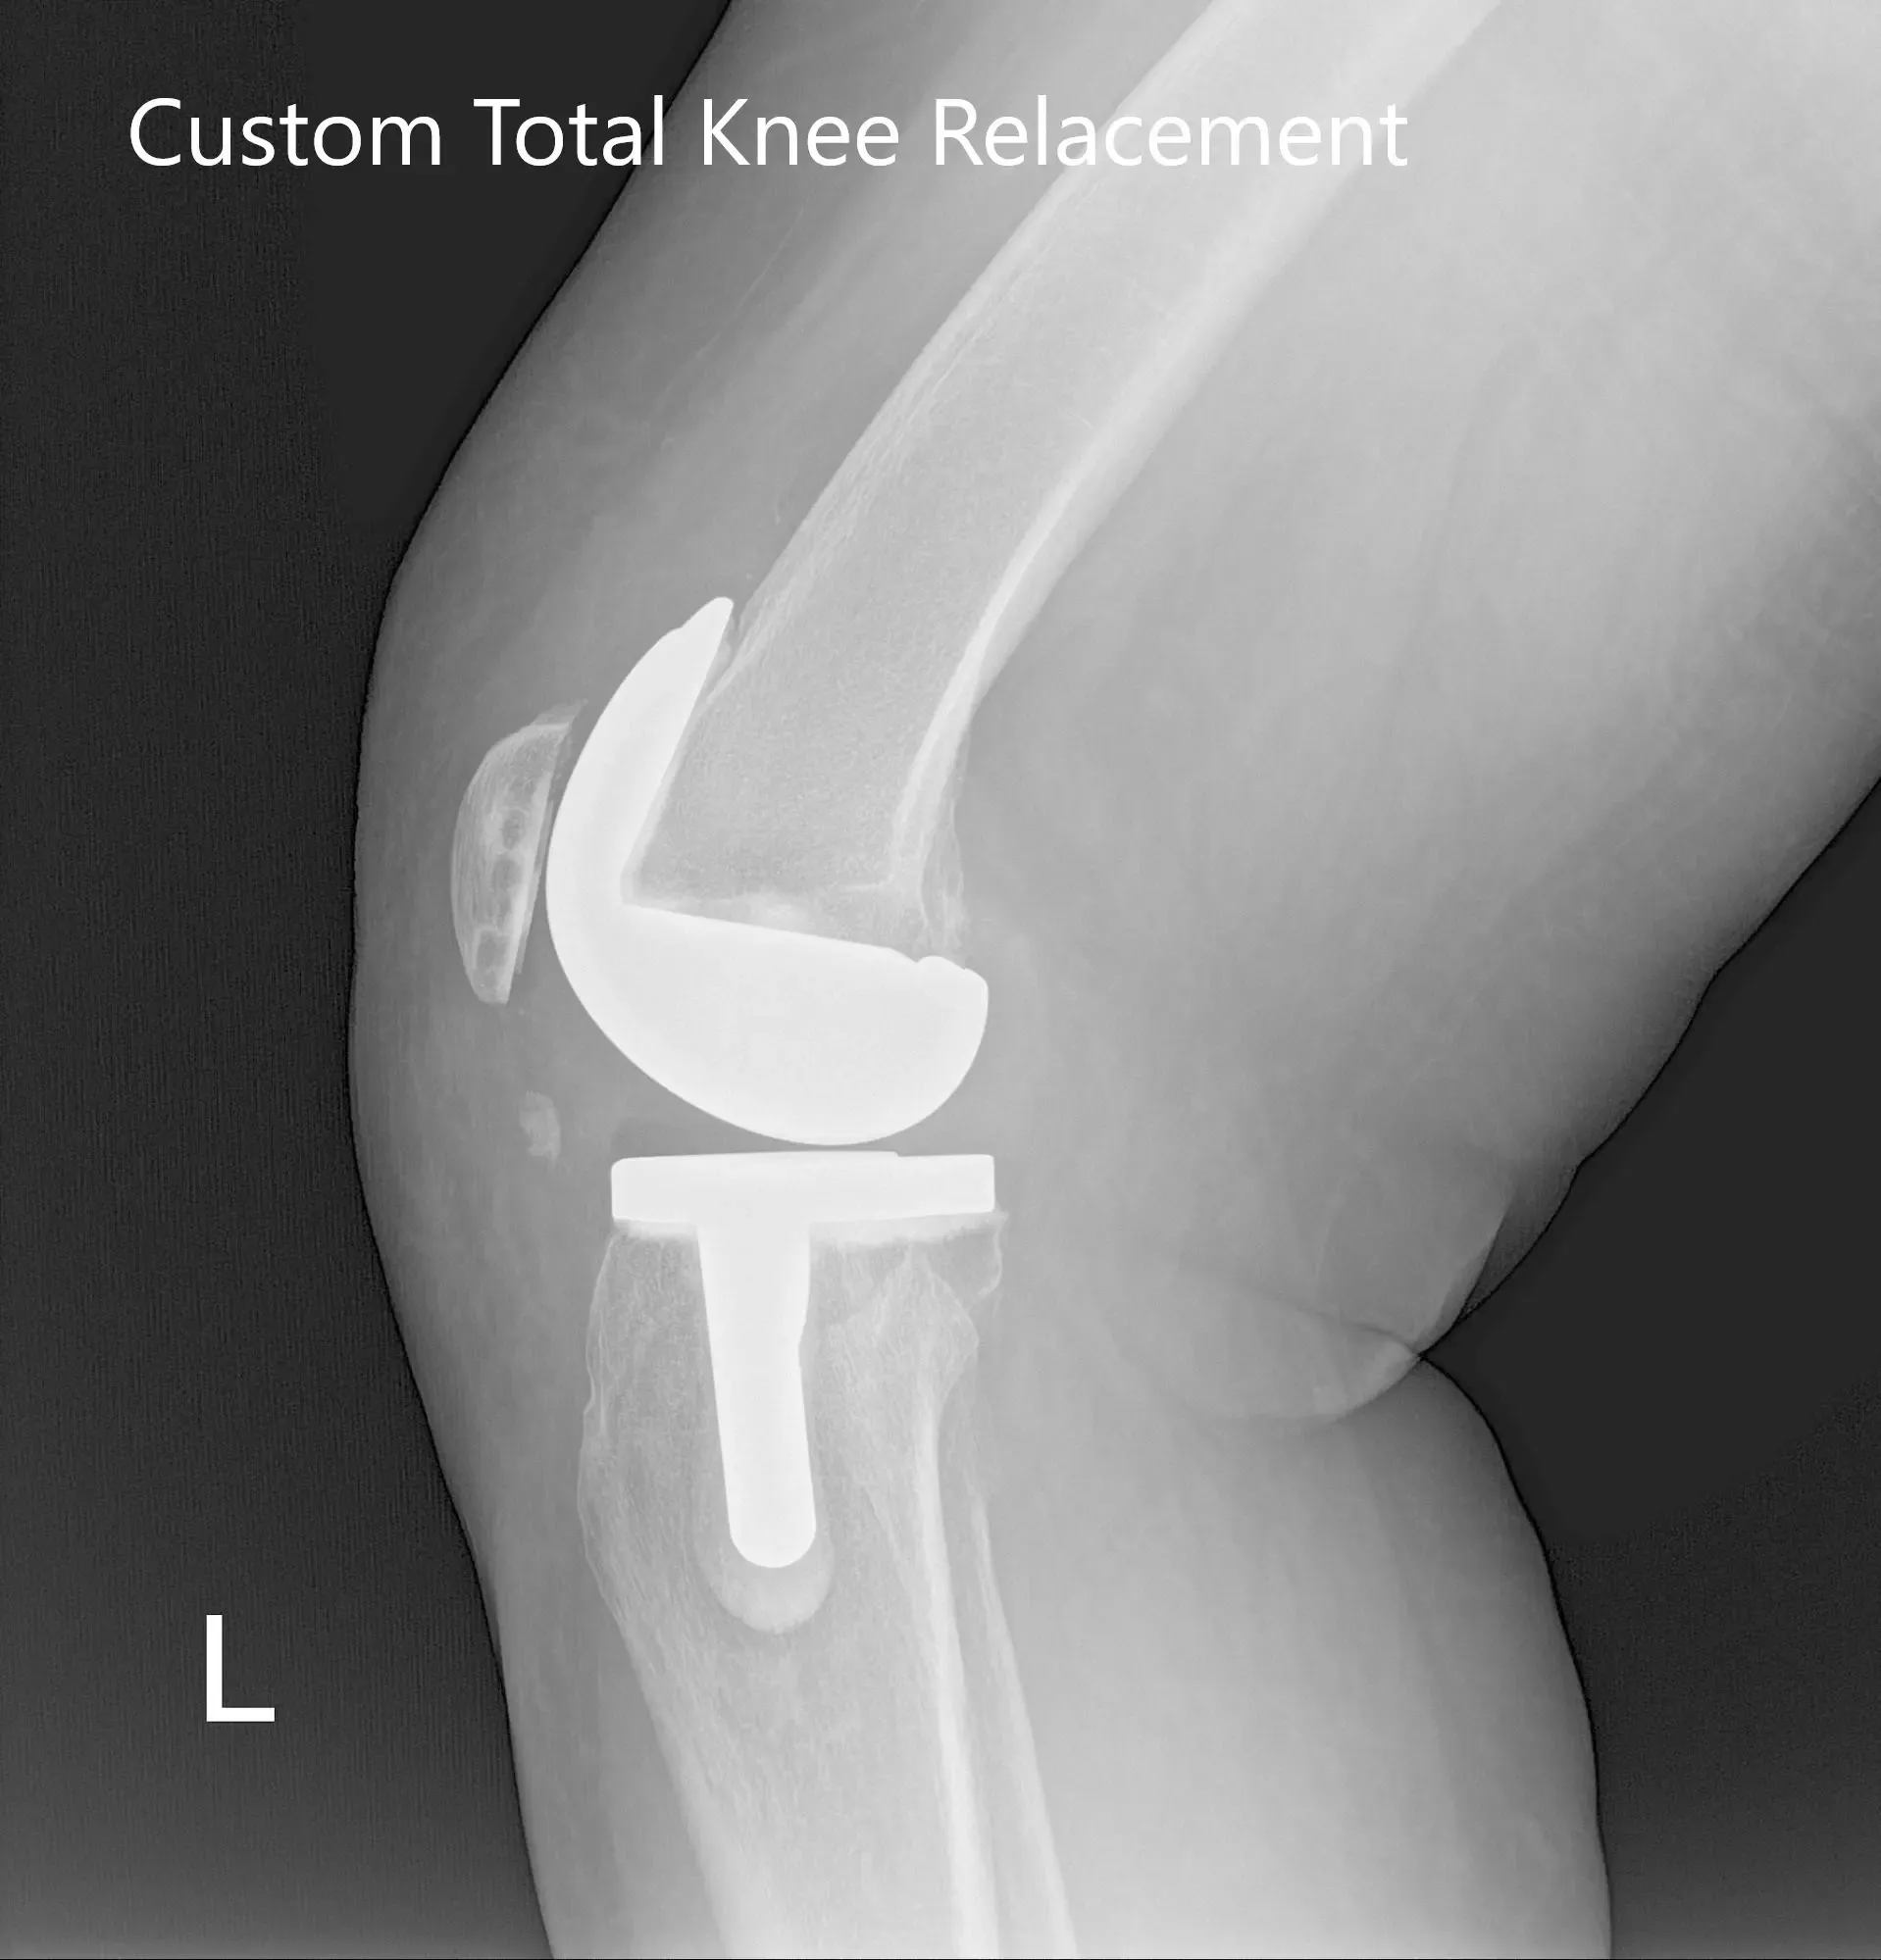

Post Operative X-Ray of the left knee showing AP and lateral view

Implants used: 8 mm posterior stabilized polyethylene with tibial tray, femoral implant 32 mm, 6 mm thickness polyethylene with an 8 mm polyethylene insert.